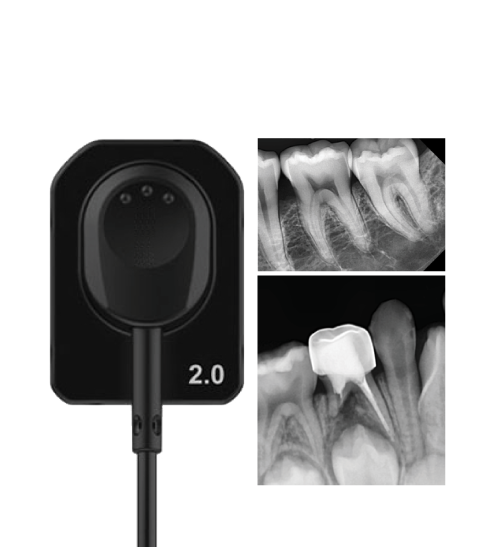

GET FREE

X-RAY & SENSOR

GET FREE

X-RAY & SENSOR